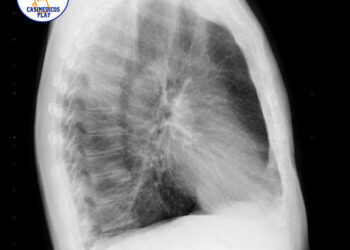

Introducción y descripción del caso

Mujer de 34 años. Es dependienta de una tienda de modas. El único antecedente clínico es artritis reumatoide desde hace 5 años, controlada con metrotrexate y sin brotes desde hace 2 años. No tiene hábitos tóxicos. Al final de una consulta rutinaria, refiere que desde hace 3 días presenta dolor abdominal bajo de tipo cólico, de intensidad leve, no relacionada con un cambio de habito intestinal, ni con trasgresión dietética, ni con alteración menstrual.

Se observa una perdida de peso leve,( 3 kg), en los últimos tres meses, aunque refiere que lleva mucho estrés en el trabajo y come mal. No presenta síndrome miccional ni fiebre ni otras sintomatologías. La exploración abdominal es anodina, se solicita hemograma y bioquímica general, test de sangre oculta en heces. Se pauta dieta y espasmolíticos, y observación domiciliaria. Al día siguiente vuelve a consultar por el dolor abdominal, aunque refiere que es más intenso, y que se va acompañado de nauseas y un vomito, y una deposición blanda con hebras de sangre. En la exploración abdominal presenta un abdomen poco depresible, dolor en fosa iliaca derecha, con Signo de blumberg positivo, por lo que se remite a Urgencias hospitalarias con diagnostico de abdomen agudo. Es valorada por el cirujano decidiéndose intervención quirúrgica, detectándose un plastron inflamatorio abscesificado a nivel de ileon distal y colon proximal, se hace resección parcial, siendo dada de alta 10 días después. Actualmente lleva 3 meses estable y sin nueva crisis.